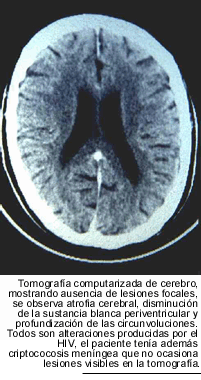

es normal. Por el contrario, el examen microscópico directo, del sedimento

de LCR, con tinta china, acusa la presencia de levaduras capsuladas en el 80

% de las muestras. La tomografía computarizada del encéfalo no

exhibe, habitualmente, masas ocupantes. Las alteraciones observadas suelen ser

las determinadas por el HIV: atrofia cerebral, aumento del espacio subaracnoideo,

así como del tamaño de los ventrículos y con menos frecuencia,

signos de vasculitis. La resonancia nuclear magnética, muestra en algunos

casos la presencia de pequeñas lesiones nodulares situadas en la base

del encéfalo.